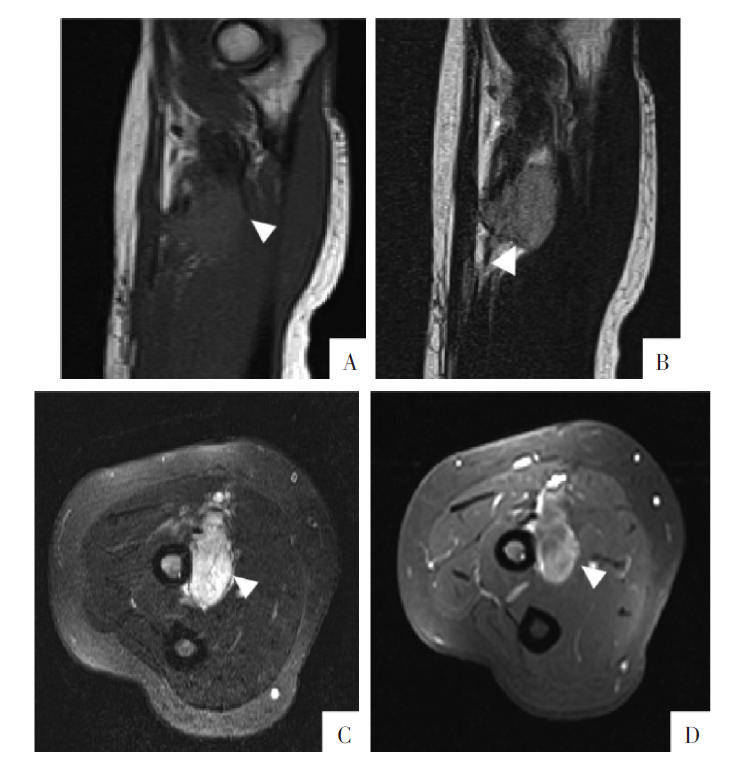

图5

病人女,51岁,肘关节软组织透明细胞肉瘤。A图,矢状面T

1

WI上可见桡骨近端内侧软组织内占位,信号略高于肌肉。B、C图分别为矢状面T

2

WI和横断面T

WI-FS,可见病灶内条、线状低信号。D图,横断面增强影像显示病灶不均匀强化。